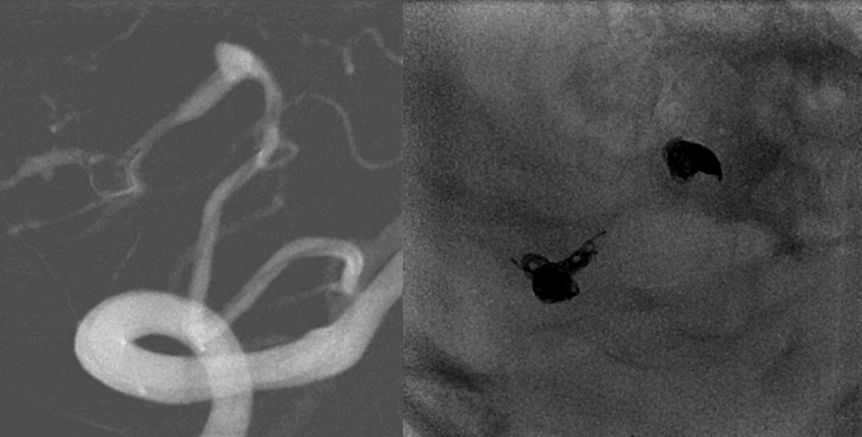

在150cm超滑泥鳅导丝的导引下,经6F动脉鞘,将6F导引导管(Codman 6F Envoy)超选入右侧椎动脉V2段。导引导管位置满意后,接高压肝素盐水持续稳定滴注。调整至合适的工作角度后,路图引导下由Synchro--14微导丝将 Headway17微导管超选进入远端动脉瘤中。经动脉瘤内预置的微导管快速送入弹簧圈(ev3 3mm*8cm)成篮良好,继续送入数枚弹簧圈,工作位造影及标准正侧位造影显示动脉瘤填塞完全,退微导管至近端动脉瘤后同样送入弹簧圈数枚,并闭塞载瘤动脉,之后撤出各级导管系统顺利,正侧位造影可见动脉瘤及载瘤动脉栓塞完全,结束手术。

图4 术前术后对比,动脉是栓塞完全,载瘤动脉闭塞完全